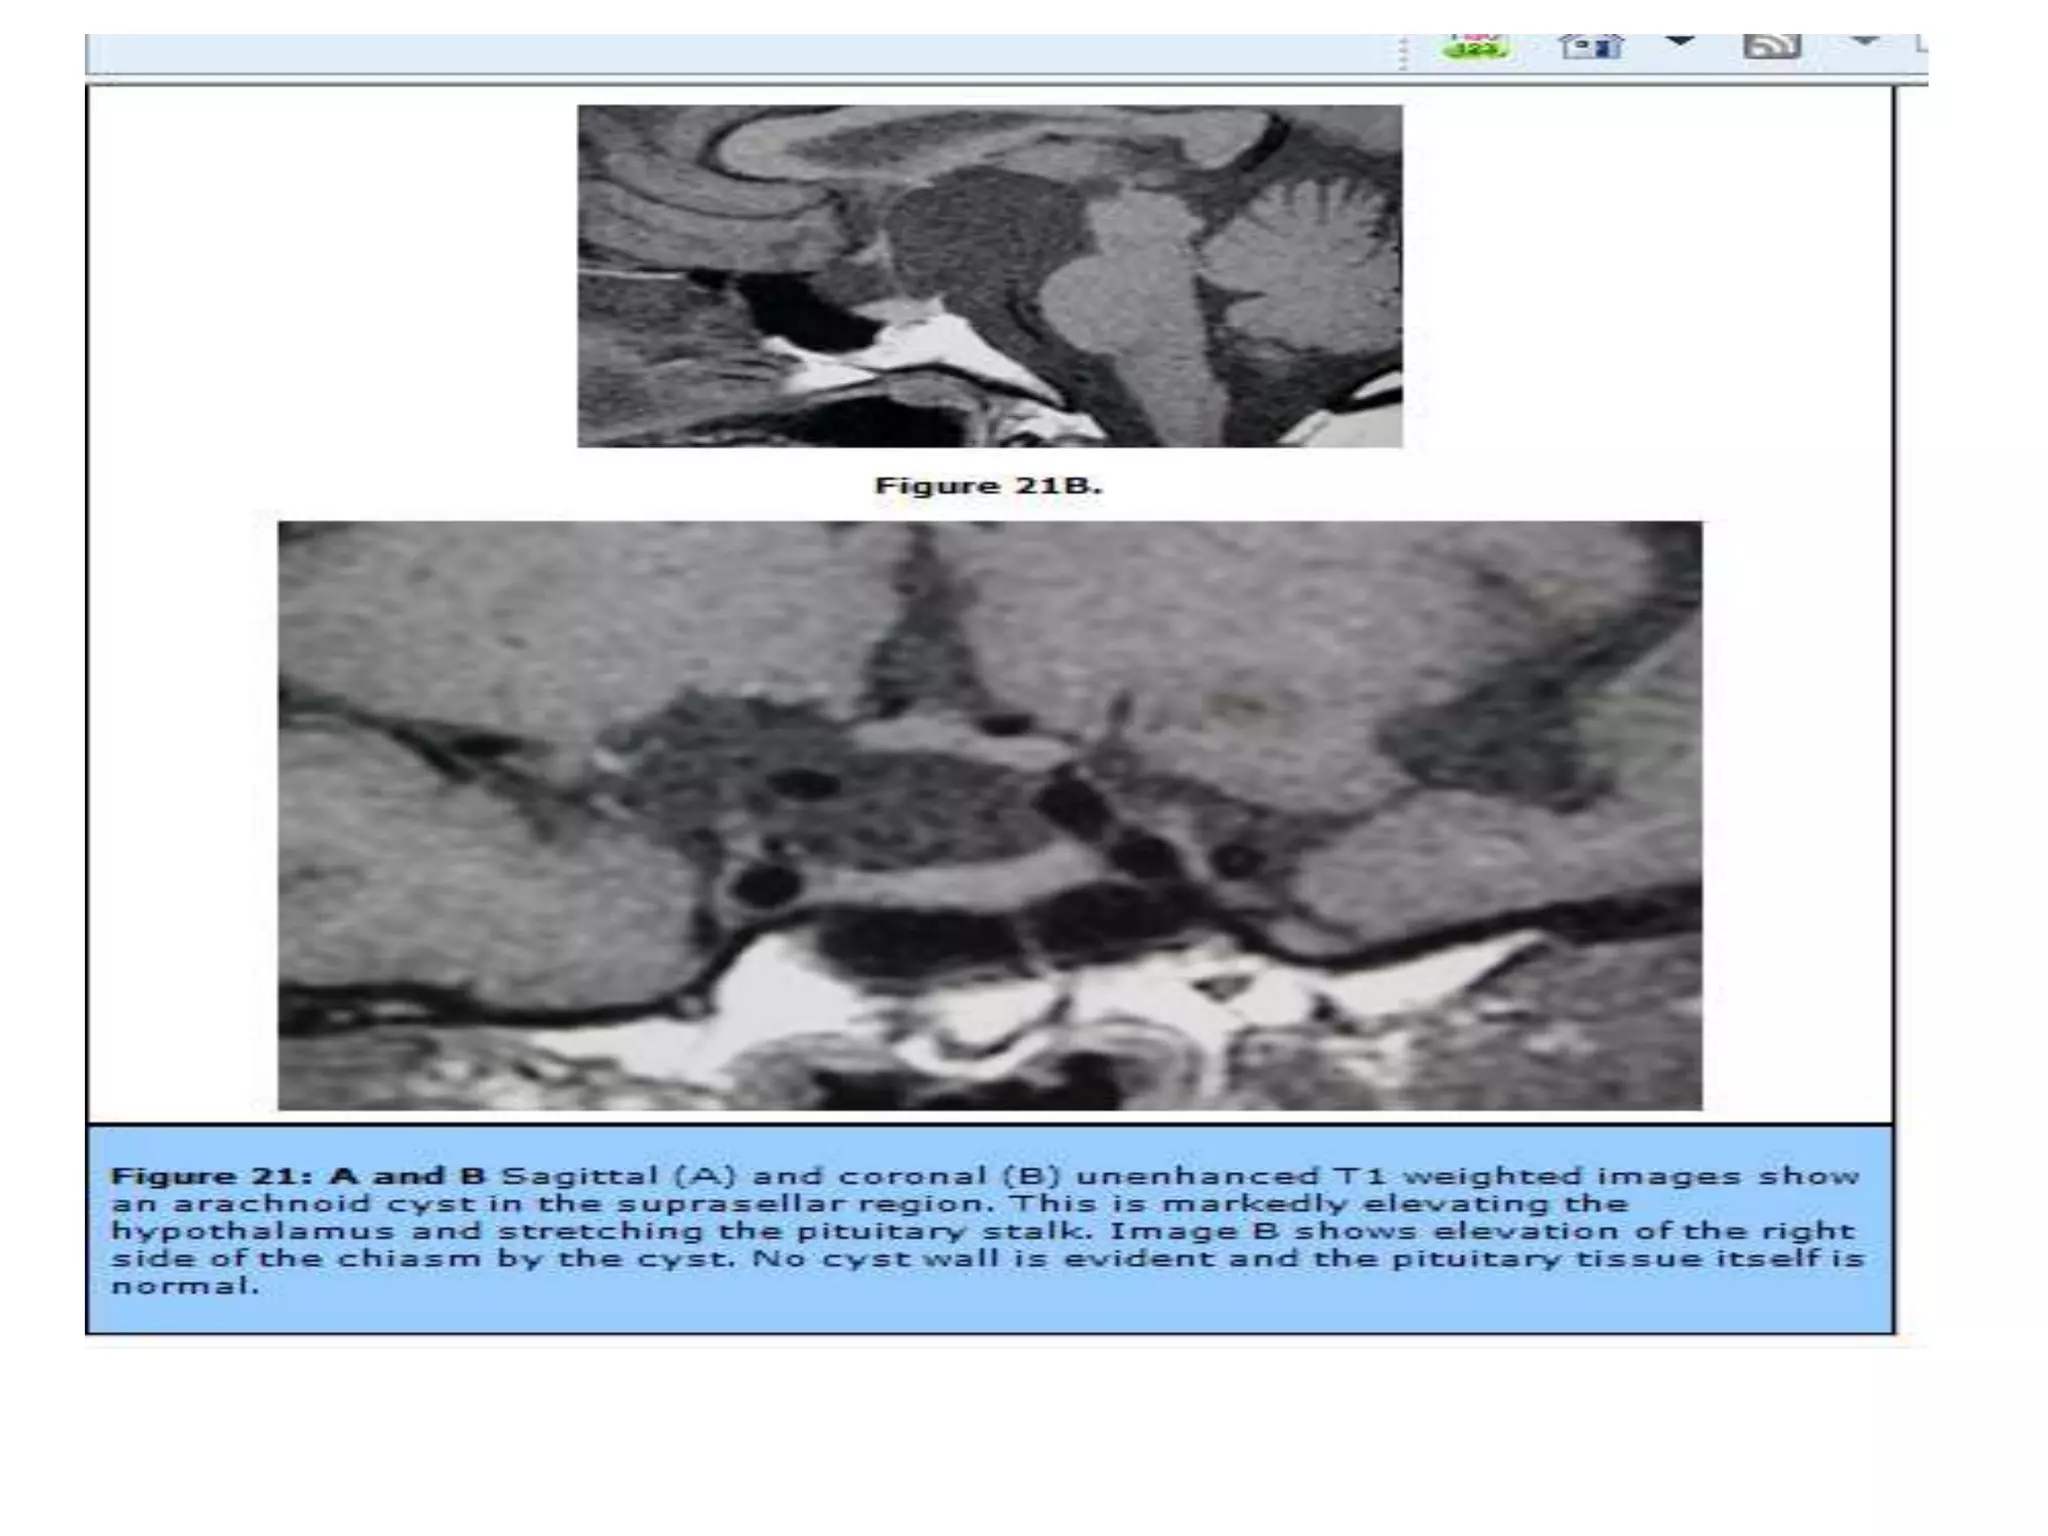

Intra-sellar arachnoidal cyst resulting in an “empty-sella” (coronal and sagittal

imaging). No displacement of the stalk.